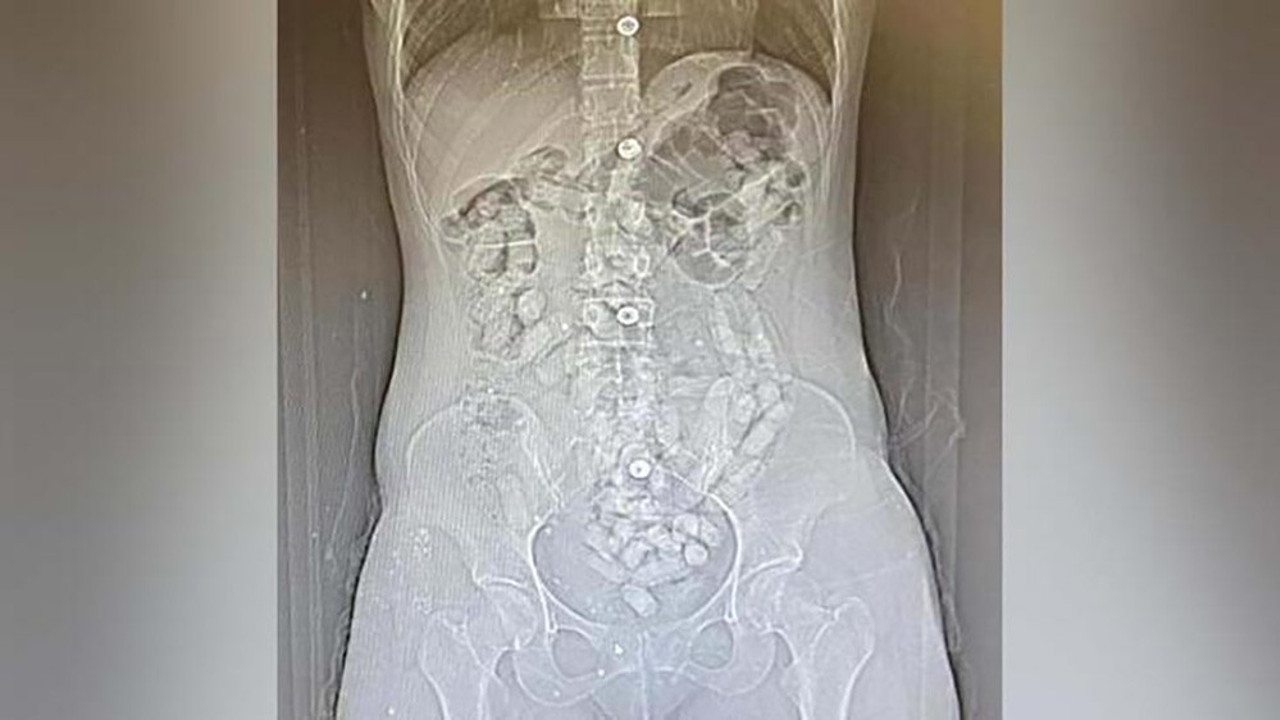

Savcılıktan alınan kararla götürüldükleri hastanede yapılan tomografi çekiminde, Khadıjeh S.''nin mide ve bağırsak bölümünde 31 parça halinde yaklaşık ağırlığı 252,52 gram ile Samıra T.''nin de 64 parça halinde 440,78 gram olmak üzere toplam 95 parça halinde 693,3 gram Afyon sakızı ele geçirildi.